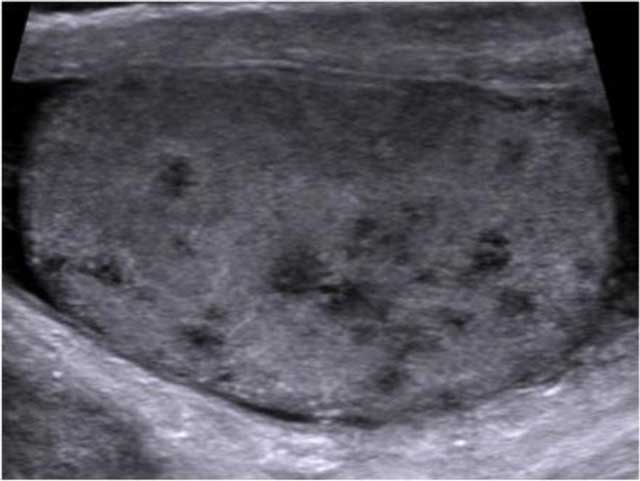

Figure 2

Longitudinal US image of the left testis shows multiple small hypoechoic nodules (< 2–3 mm) corresponding to TBC granulomas in a miliary pattern.